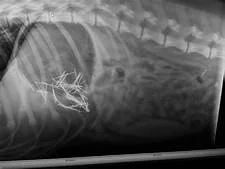

Johnes Disease - HiHealth Herdcare - Duration. Penetrating foreign bodies may cause mild to severe peritonitis penetrate the diaphragm to cause pleuritis or pericarditis or cause localized abscesses in the thorax or abdomen. Hardware disease in cattle also known as bovine traumatic reticuloperitonitis is one of the most overlooked phenomena by cattle farmers.

The disease is common when green chop silage and hay are made from fields that contain old rusting fences or baling wire or when pastures are on areas or sites where buildings have recently been constructed burned or torn down. The most common signs of hardware disease are abdominal pain and discomfort. Hardware Disease occurs after an animal ingests a metallic object that then perforates the wall of the reticulum.

Hardware Disease of Cattle opens in new window Clinical symptoms and diagnosis. Cattle are prone to ingesting metal objects that can cause problems in the digestive tract heart.

Hardware Disease occurs after an animal ingests a metallic object that then perforates the wall of the reticulum. It is an injury to the reticulum caused by ingestion of such things as small pieces of wire nails staples and other small metal objects. Farmers are often quick to deal with bacterial viral or fungal diseases but ignore hardware disease which is just as devastating. Because these objects are most often metal a common term for this problem is hardware disease. Hardware Informatics The electronic and mechanical non-software components of a computereg central processing unit monitor disk drives keyboard peripheralseg printer modem scanners Orthopedics Any deviceeg nut bolt pin plate screw and wire placed in bone to stabilize a fracture or to anchor a prosthetic joint. Biobest Laboratories 1268 views. What Is Hardware Disease. About Press Copyright Contact us Creators Advertise Developers Terms Privacy Policy Safety How YouTube works Test new features 2020 Google LLC. Hardware disease in cattle also known as bovine traumatic reticuloperitonitis is one of the most overlooked phenomena by cattle farmers.

Hardware disease is the common name for traumatic gastritis and traumatic reticulates. Cattles that have traumatic gastritis are classified into three groups sub-acute local chronic and acute diffuse type. As of right now there are two types of intervention for. About Press Copyright Contact us Creators Advertise Developers Terms Privacy Policy Safety How YouTube works Test new features 2020 Google LLC. Penetrating foreign bodies may cause mild to severe peritonitis penetrate the diaphragm to cause pleuritis or pericarditis or cause localized abscesses in the thorax or abdomen. The disease is common when green chop silage and hay are made from fields that contain old rusting fences or baling wire or when pastures are on areas or sites where buildings have recently been constructed burned or torn down. Opens in new window Treatment.